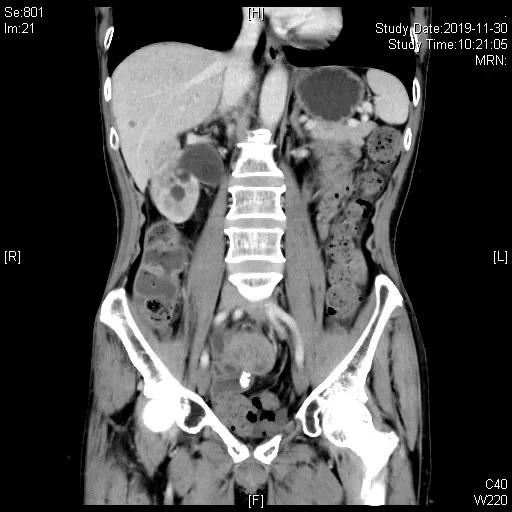

一线治疗:2019-05-21 “吉西他滨1.2d1,d8+卡铂500mgd2”化疗1周期,06-17 “吉西他滨1.4d1,d9+奥沙利铂200mgd2”化疗1周期。07-12胸腹部CT及盆腔MRI评估近期疗效为完全缓解(CR)。于07-12至10-05共计“吉西他滨1.4d1,1.2d14+奥沙利铂200mgd2”化疗4周期,III°血小板减少及白细胞减少,影像学评估CR。11月底出现造瘘口出血, 11-30胸腹部CT示回肠代膀胱壁增厚伴软组织肿块,考虑再次复发。

一线化疗6周期结束后40天评估,评估PD